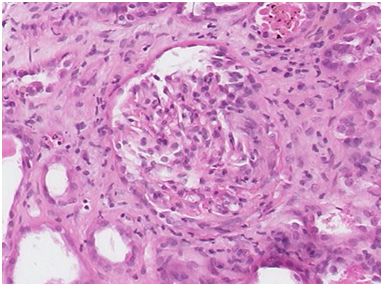

After about a week there was no improvement in the patient’s condition. By this time, the c-ANCA was reported as positive. Hence, a diagnosis of Wegener’s granulomatosis was made. He was then transferred to the internists’ care. Although the patient was out of our care but for the sake of interest rest of his clinical course is described from this point. Soon, he developed acute renal failure and in a matter of five days, his urea increased from 4.9mmol/L to 51mmol/L and serum creatinine to 1200umol/L. There was significant proteinuria of 6g/dl. He required hemodialysis for about two weeks and also a few sessions of plasmapheresis. His renal biopsy was done that showed crescentic glomerulonephritis (Figure 3). The nasal biopsies were sent for second opinion and also demonstrated vasculitis (Figure 4). He was put on pulsed intravenous cyclophosmamide 0.4mg/m2 and oral prednisolone 80mg OD followed by oral cyclophosmamide 100mg OD and prednisolone 60mg OD. Soon the general condition of the patient improved and his renal profile also became normal. He was then managed on out-patient basis on maintenance therapy of cyclophosmamide and prednisolone in varying doses ranging from 50-100mg OD and 20-40mg OD respectively depending upon the disease activity. For example, he had ‘flares’ of the disease in the form of left exudative pleural effusion that needed multiple tapping. It finally resolved. Then, he had left pneumothorax that was encysted (Figures 5 & 6) and it resolved on its own. Currently, 7-years on, the patient is in clinical remission and follows every month with us for decrusting of nose due to severe atrophic rhinitis.

Figure 4 Nasal biopsy showing vasculitis.